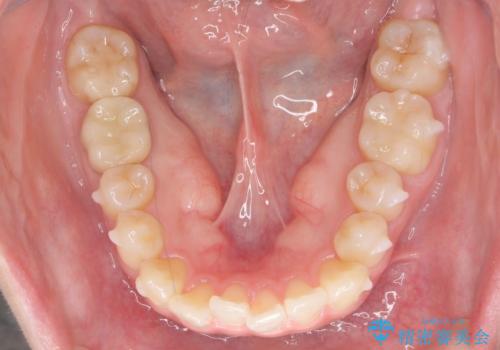

- 前歯のがたつきをきにされていました。

上下の前歯をやすりがけする処置(IPR)を行い、前歯の並びを出っ歯にしないようにしながら整えました。

症状が軽度であるためモニター採用になりました。